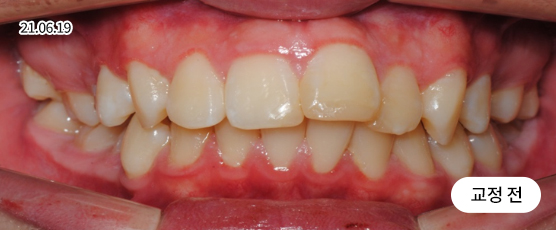

매복치 Solution

매복치는 잇몸 속에서 인접 치아에 손상을 줄 수 있어

치아 견인을 통해 제자리를 찾아주어야 정상적으로 치아가 자리 잡을 수 있습니다.

* 치근흡수, 잇몸퇴축 등 부작용이 발생할 수 있습니다.

* 본 사진은 동일 조건에서 촬영되었으며, 환자 본인의 동의를 얻어 게재되었습니다.